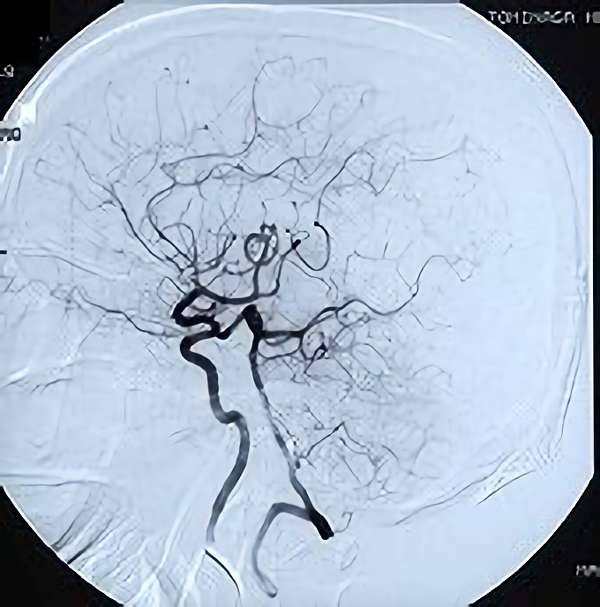

脳血管撮影

手術前

手術後